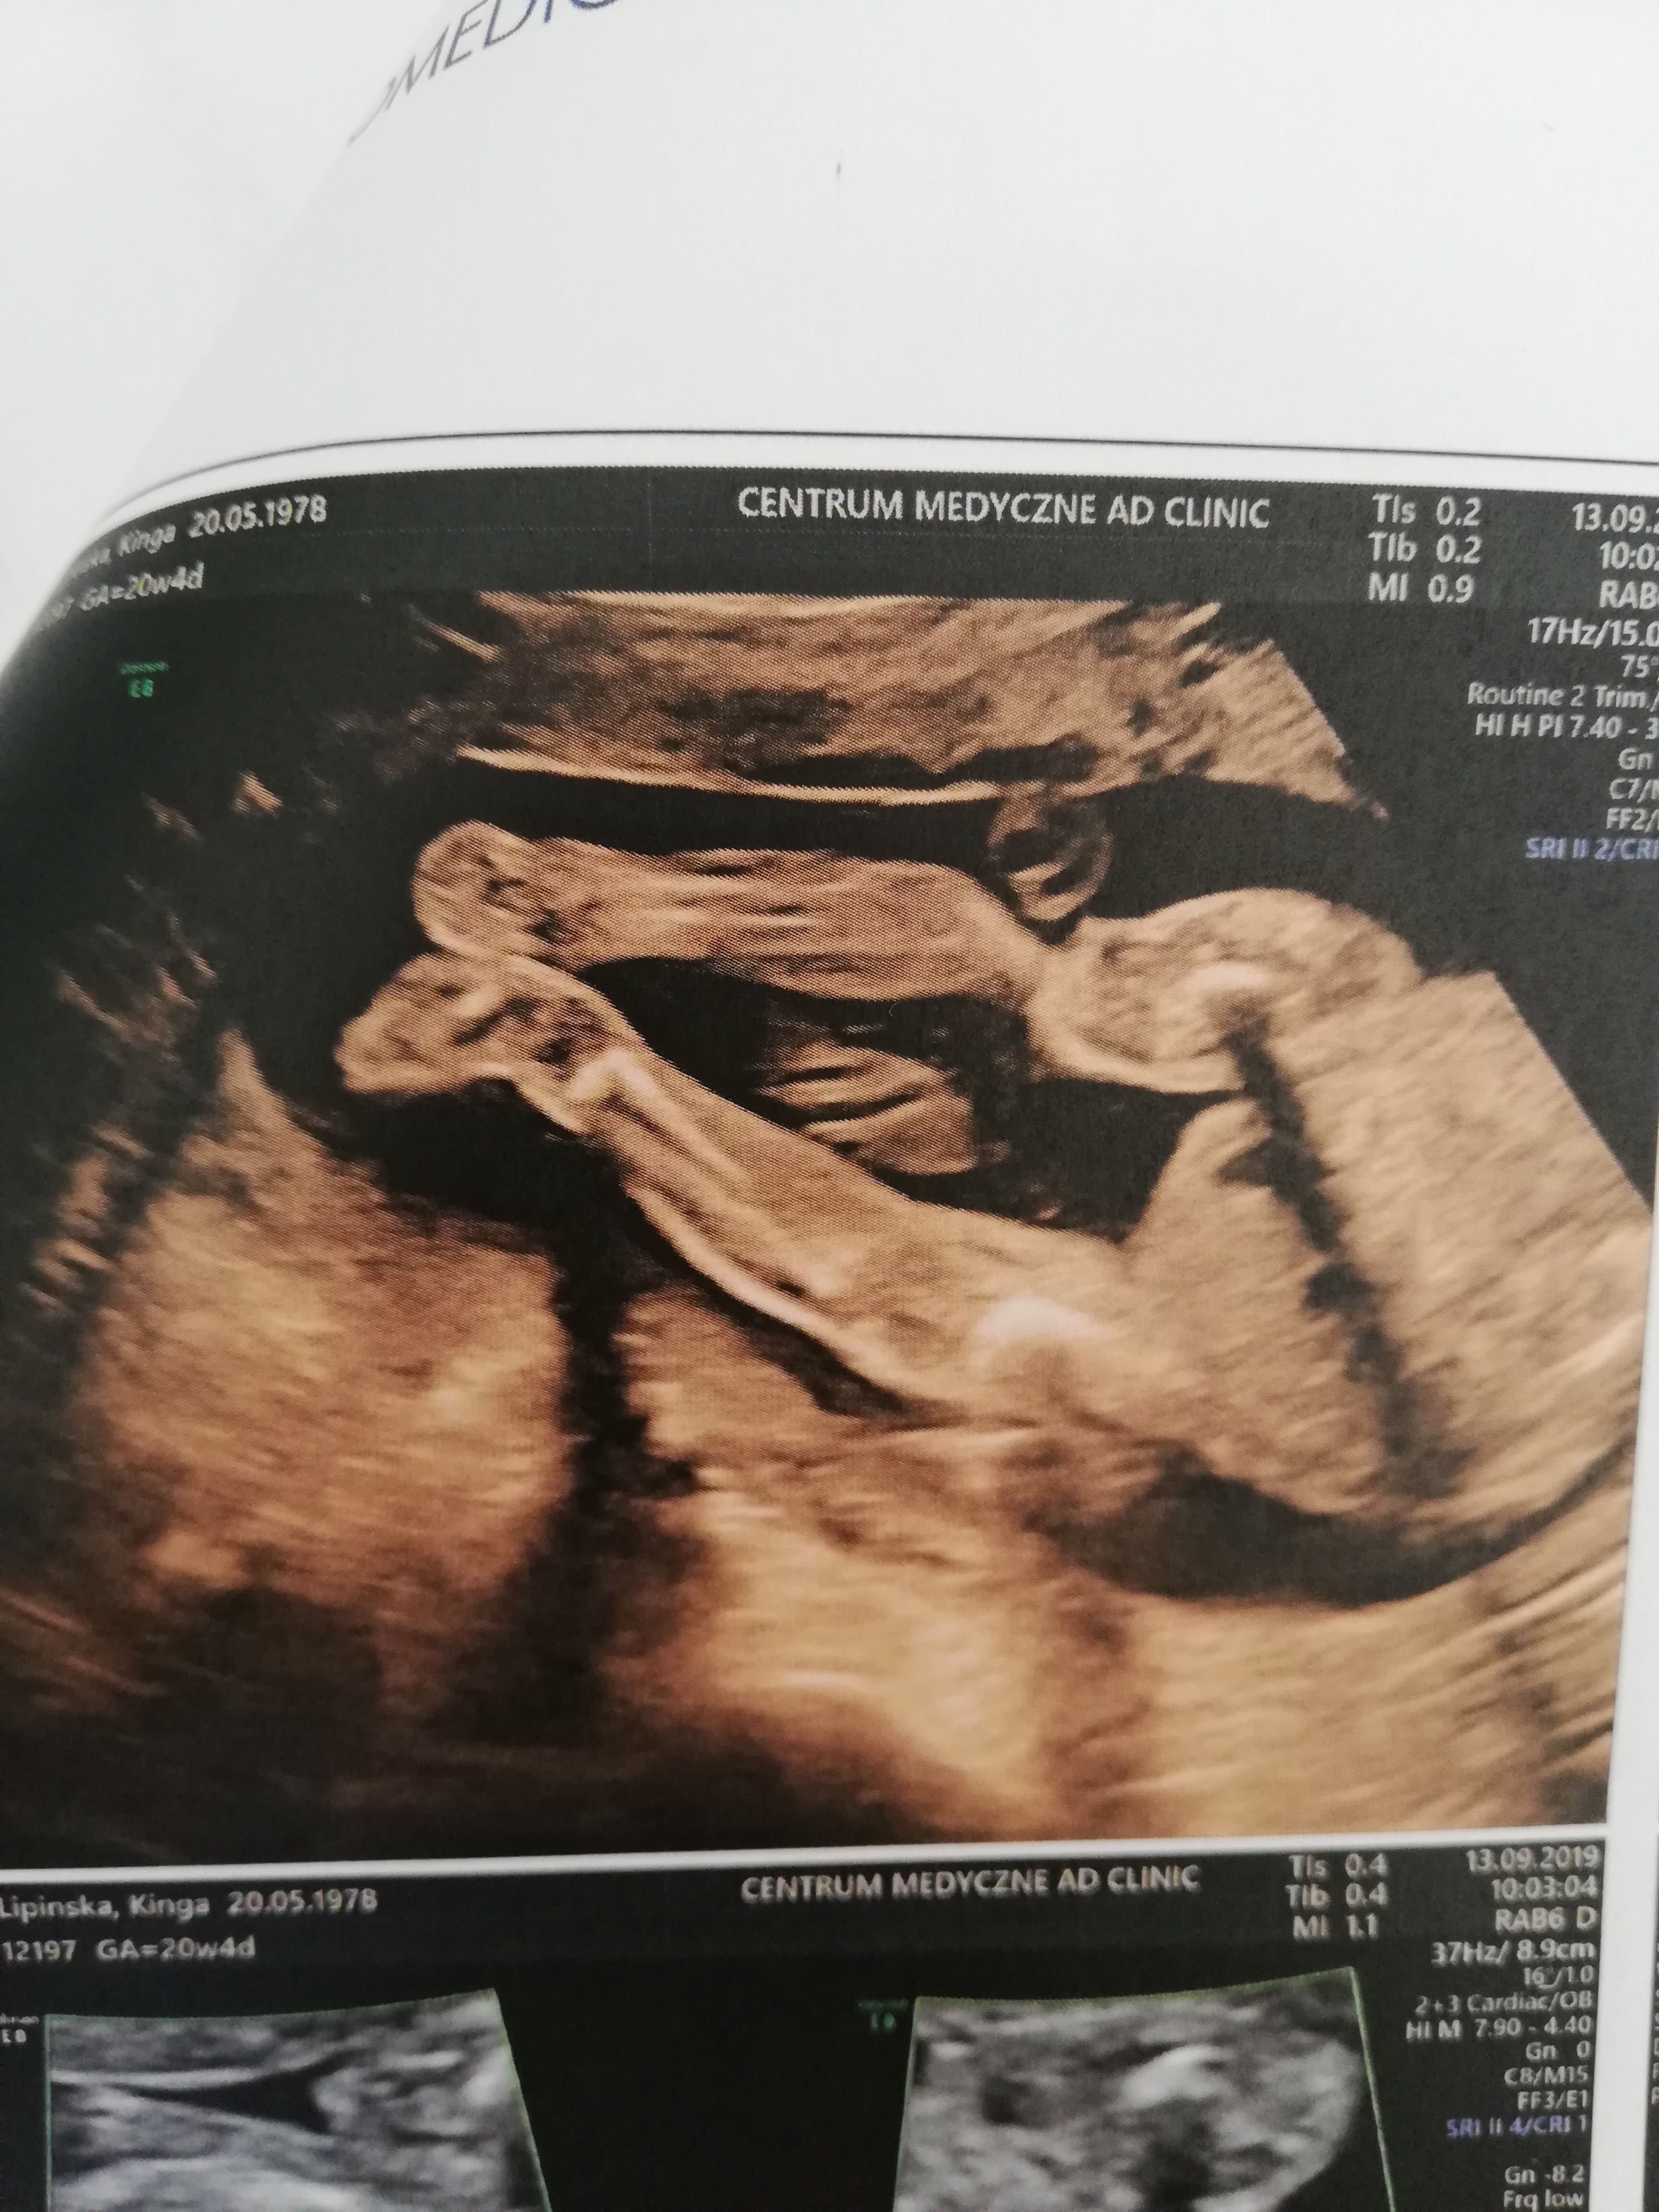

My nareszcie po badaniach prenatalnych :D

Józef zdrowy jak ryba i długaśny, czyli marne szanse na urodzenie dziecka mniej jak 3500g.

Wyszedł miarami poza siatki centylowe.

503g i 15,5 cm :D dwa tygodnie do przodu.